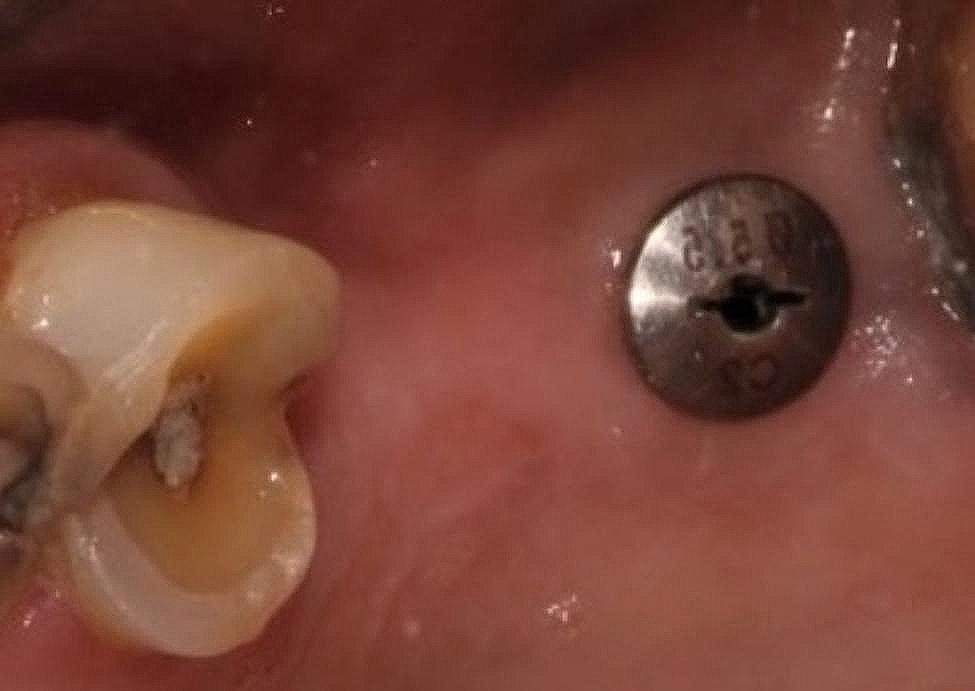

Fig. 2.

Healing cap placed